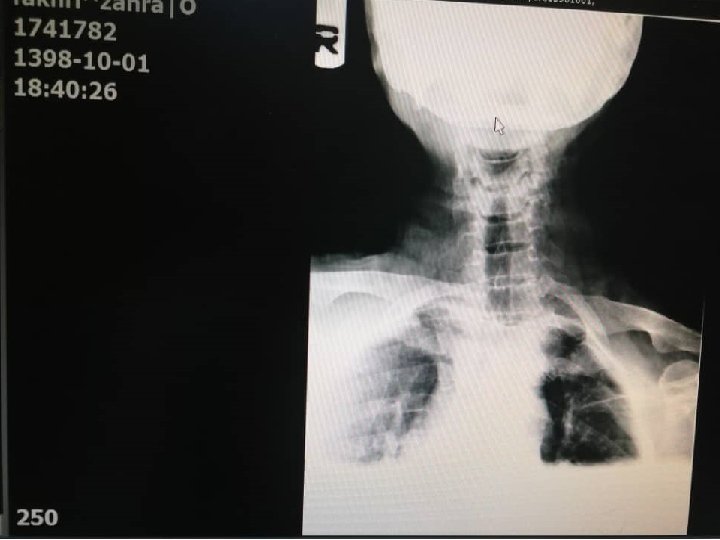

CT Scan axial of neck with and without IV Contrast 98/6/9